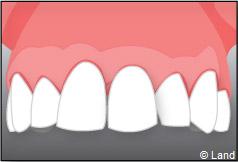

Pour finir, une prothèse sera mise sur cet implant qui se comportera comme une racine artificielle.

Exemple d’un implant unitaire pour remplacer une dent antérieure manquante.